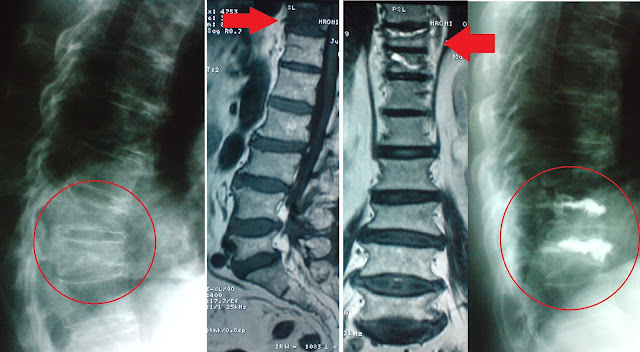

Περίπτωση 2:

Η γυναίκα 78 ετών με οστεοπόρωση υπό θεραπεία για περισσότερα από 15 χρόνια. Είχε πάρει από όλες τις κατηγορίες των αντιοστεοπορωτικών φαρμάκων. Τα τελευταία 2 χρόνια έκανε ενέσεις παραθορμόνης. Παρόλα αυτά συνέχιζε να παθαίνει κατάγματα και να υποφέρει από πόνους. Απαλλάχθηκε από τον πόνο μετά από σπονδυλοπλαστική σε δύο επίπεδα με τοπική αναισθησία.